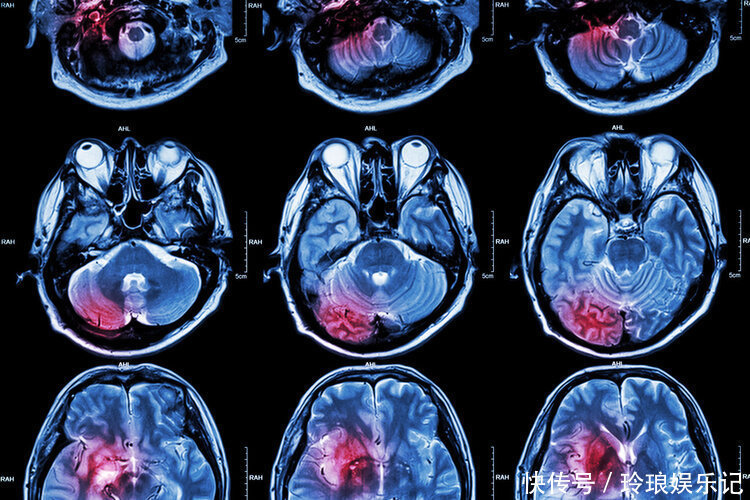

“太惊险了,刚才的那个病人差点死在手术台上了。”“是啊,还好送来的及时,就差一点了。”下了手术台,两位医生喝着茶,讨论着刚才九死一生的场面。魏先生就是在这两位医生的妙手下,被救回来的,事后魏先生还开玩笑地说:“阎王爷已经把我的名字写到花名册上了,还好我命大。”魏先生是在家中洗澡时候摔倒的,被送到医院的时候已经昏迷。经急诊科的医生检查,发现魏先生已经明显出现一侧瞳孔放大、对光丧失反应的症状,颅脑CT显示存在大面积脑出血现象,之后被紧急转入神经外科治疗,经过医生进行颅内血肿清除术、脑内减压以及骨瓣减压术之后,魏先生的各项体征恢复正常,经过14天已经完全可以正常交流。纵观魏先生的发病原因,正是因为长期高血压控制不当引起的脑出血。

一、高血压,脑出血的“定时炸弹”高血压脑出血是高血压很常见的一种并发症,占所有脑卒中的10-20%。我国是高血压发病极高的国家,报道显示,我国的高血压患者人数高达一亿,但是可以控制好的仅仅有5%。研究发现,脑出血的发生跟高血压有着紧密的联系,而高血压又会进一步影响到脑出血的恢复。高血压之所以引发脑出血,是当血压突然升高时候,大脑内的血压也会随之升高,当血管内压力变大已经超过血管可以承受的范围之后,就会造成血管破裂。在脑内的血管中,有一个豆纹动脉,直角转弯地方出现血压升高时很容易出血。